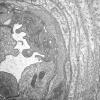

VASCULAR

Hypoxia-Ischemia, fetal-neonatal

White Matter (11)